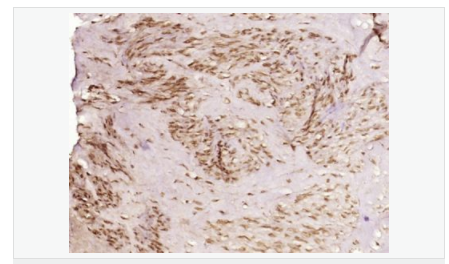

產(chǎn)品應(yīng)用IHC-P=1:100-500 IHC-F=1:100-500 ICC=1:100-500 IF=1:100-500 (石蠟切片需做抗原修復(fù))

細(xì)胞定位細(xì)胞核 細(xì)胞漿